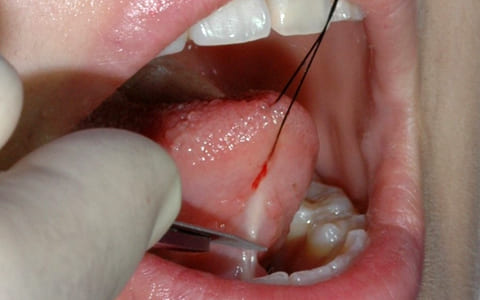

小帯を延長するために舌を上下にけん引しながら、メスで小帯を切離し、延長する。

STEP.03

舌を糸で牽引して舌小帯にメスを入れて切開する -

STEP.04

切るという感じではなくメスを当てることで切開部が広がっていく感じである